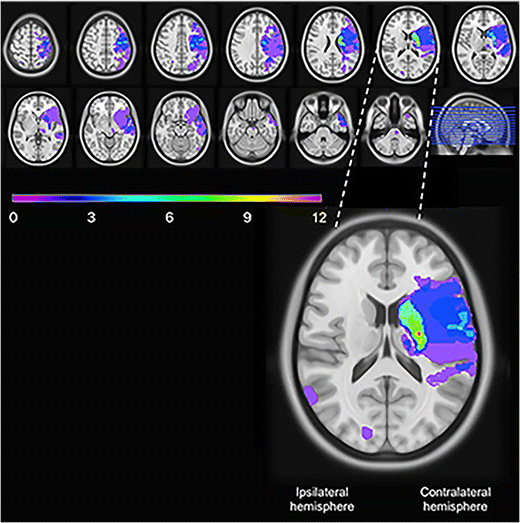

Frequency and Characteristics of Stroke Patients with UEMI

Among the 76 stroke survivors with no recurrent stroke, 41 had UEMI at baseline of whom 10 displayed residual UEMI after 3–5 years. Analysis of the DW-MRIs showed corticosubcortical infarcts in 14/41 stroke survivors with UEMI at baseline, all involving the motor cortex and/or the estimated course of the corticospinal tract. Sole cortical infarcts were observed in 3/41 stroke survivors, all with motor cortex involvement. Moreover, only subcortical infarcts were seen in 19/41 stroke survivors, and the estimated course of the corticospinal tract was involved in 12 of these cases. In addition, 2/41 stroke survivors had brainstem infarcts (without clear localizing symptoms from the brainstem), and 3/41 had MRI negative strokes. The MRI overlap image showing the brain infarcts of the stroke survivors with UEMI at baseline is presented in Fig. 2.

Fig. 2

figure 2

Lesion overlap image of the stroke survivors with upper extremity motor impairment at baseline (n = 41 stroke survivors without recurrent stroke). The lesions were oriented such that the clinically relevant stroke lesions were assumed to be in the left hemisphere. The color bar indicates the number of overlapping lesions, and the enlarged picture shows the slice with the maximum number of overlapping lesions

To illustrate the ischemic lesions in stroke patients with UEMI, a lesion overlap map was created. The identified lesions on the DW-MRI sequences were manually drawn on the closest corresponding slices of the ICBM 2009a Nonlinear Symmetric 1 × 1 × 1 mm T1-weighted template (supplied by McConnell Imaging Center, Montreal, Canada), using MRIcron software [32, 33]. In order to simplify the overlap map, the lesions were oriented such that the clinically relevant stroke lesions were assumed to be in the left hemisphere. The lesion overlap plot was then obtained using the MRIcron software.